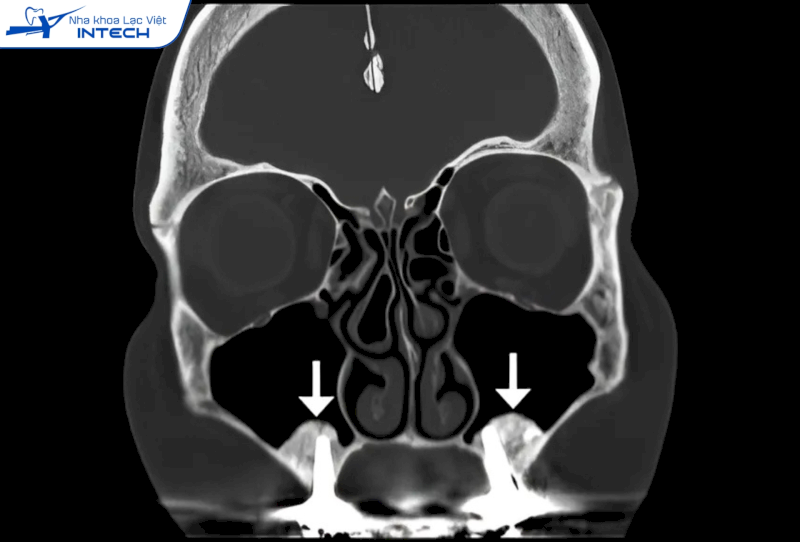

- Thủng xoang: Trong quá trình phẫu thuật, nếu bác sĩ không xác định chính xác vị trí và độ sâu khi thao tác, có thể gây thủng màng xoang, dẫn đến rò rỉ không khí hoặc dịch từ xoang vào khoang miệng, gây viêm xoang cấp tính và các biến chứng nghiêm trọng khác.

Khi cắm Implant hàm trên, nếu bác sĩ xác định sai độ sâu thì có thể cắm Implant âm phạm xoang hàm, gây nên nhiều biến chứng nguy hiểm